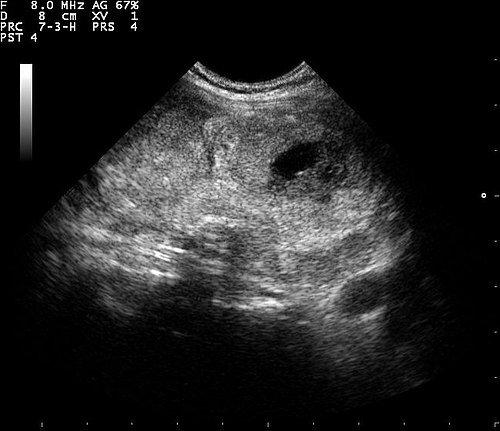

Liver phantom with multiple focal lesions including hemangioma, hepatocellular carcinoma, cyst, and metastasis for...